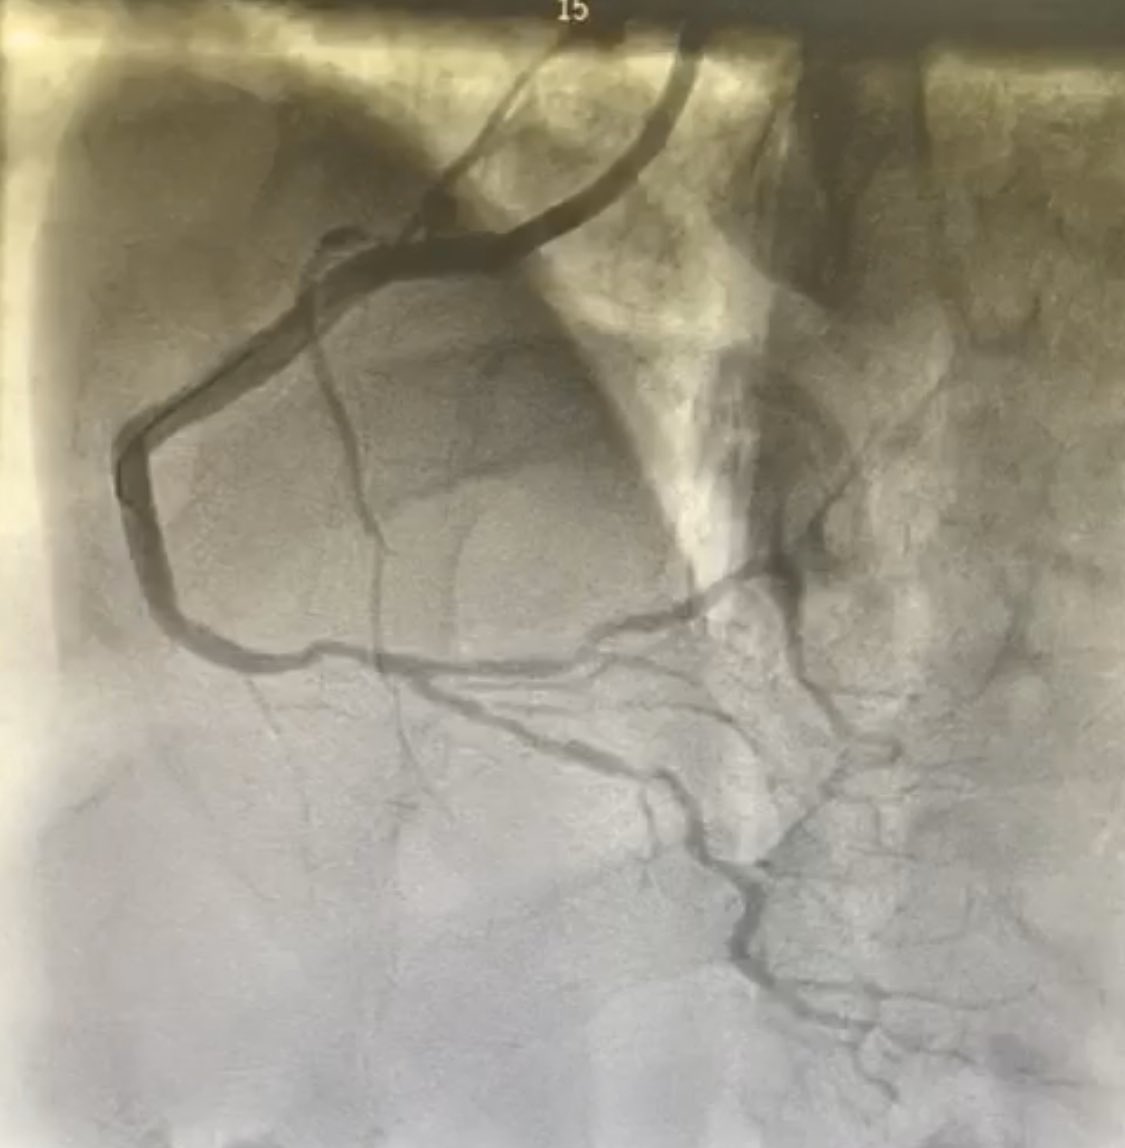

RCA stenosis Medina 1-1-1. Fielder XT-R, Supercross FT, Rotapro 1,25 mm. NSE Alpha 3,0/13 mm. TAP with Xience ProS 3,0 23 mm in RCA/RIVP and 3,0/18 mm in RPLS. Final KB. POT with Sapphire NC 24 4,0/8 mm. @BotPci #Rotapro @Obisht @KPujdak @KardiologieHH @klinki_hh @VRubesch

AndWierucki's tweet image. RCA stenosis Medina 1-1-1. Fielder XT-R, Supercross FT, Rotapro 1,25 mm. NSE Alpha 3,0/13 mm. TAP with Xience ProS 3,0 23 mm in RCA/RIVP and 3,0/18 mm in RPLS. Final KB. POT with Sapphire NC 24 4,0/8 mm. @BotPci #Rotapro @Obisht @KPujdak @KardiologieHH @klinki_hh @VRubesch